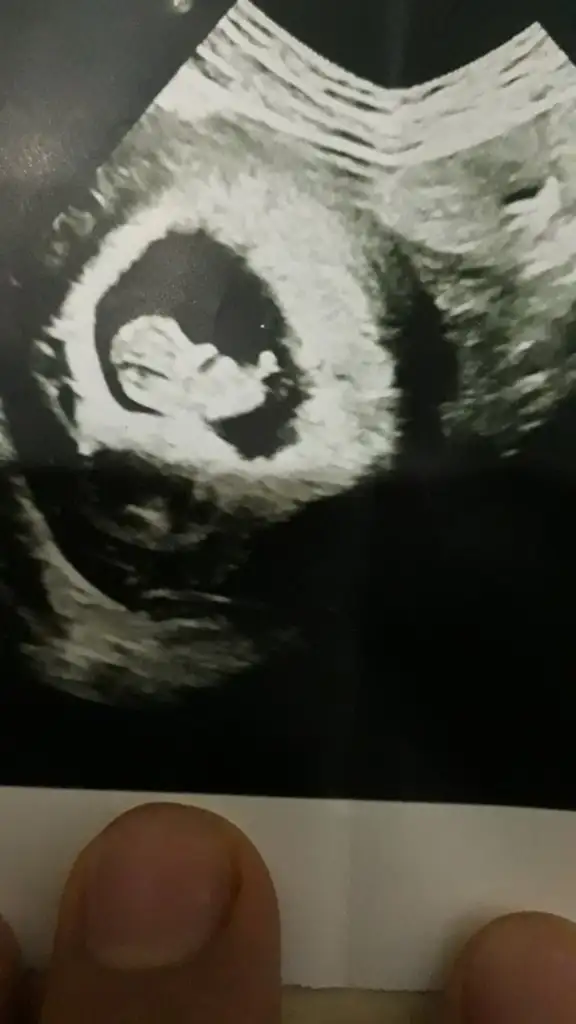

Arkadaşlar bugün karından ultrason çekildi, 6+3 , bir oğlum var ,bir de kızım olsun çok istiyorum:) bana da yorum yaparsanız çok sevinirim, heyecanla bekliyorum